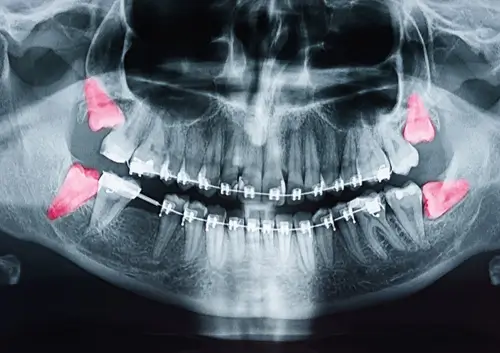

For many people, wisdom teeth become a source of discomfort or even pain at some point. These third molars, which typically emerge in the late teens or early twenties, can cause significant dental issues when they don’t align correctly or become impacted. Knowing when it’s time to have them removed is crucial to avoiding complications that could lead to more serious oral health problems. There are several key signs that indicate you might need to have your wisdom teeth removed, and addressing these signs early on can help you prevent further discomfort or damage to your mouth.

In some cases, the pain may be more intermittent, only surfacing when the teeth are trying to break through the gums. However, if the pain becomes constant or severe, it is a strong indication your wisdom teeth may be impacted, meaning they are trapped under the gums or bone. Impacted teeth can lead to infections, cysts, or other complications if not addressed.

Even if your wisdom teeth aren’t causing immediate pain, they can still lead to long-term dental issues by crowding or shifting other teeth in your mouth. Wisdom teeth often don’t have enough room to grow in properly, which forces them to push against surrounding teeth. This pressure can cause misalignment, which may lead to the need for braces or other orthodontic treatments to correct the shifting.

Another significant sign your wisdom teeth may need to be removed is recurring infections around the teeth, often due to a condition known as pericoronitis. This happens when the gums surrounding a partially erupted wisdom tooth become inflamed and infected, leading to pain, swelling, and difficulty chewing. If not treated, this infection can spread to other areas of the mouth, leading to more serious health concerns.